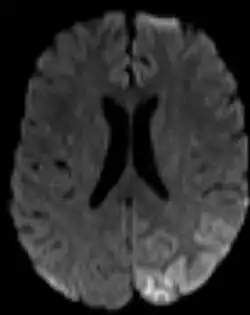

Dans le domaine médical, une hypoperfusion est une diminution de débit sanguin (à distinguer de l'« hypovolémie », une diminution du volume sanguin) dans un territoire de l'organisme. Dans les cas graves elle peut induire un état de choc, des nécroses tissulaires, la démence (quand elle concerne le cerveau), voire la mort.

Ce mot désigne le plus souvent l'ischémie cérébrale, la baisse de la vascularisation d'une région du cerveau (qui semble être à long terme un facteur de démence et de maladie d'Alzheimer[1])

Dans un diagnostic, le mot est souvent associé à une description géographique de la partie de l'organe touché, par exemple une « hypoperfusion pariéto-temporale droite » désignera un débit sanguin diminué dans la partie du cerveau située à hauteur du pariétal (en haut), à droite, et au niveau des tempes.